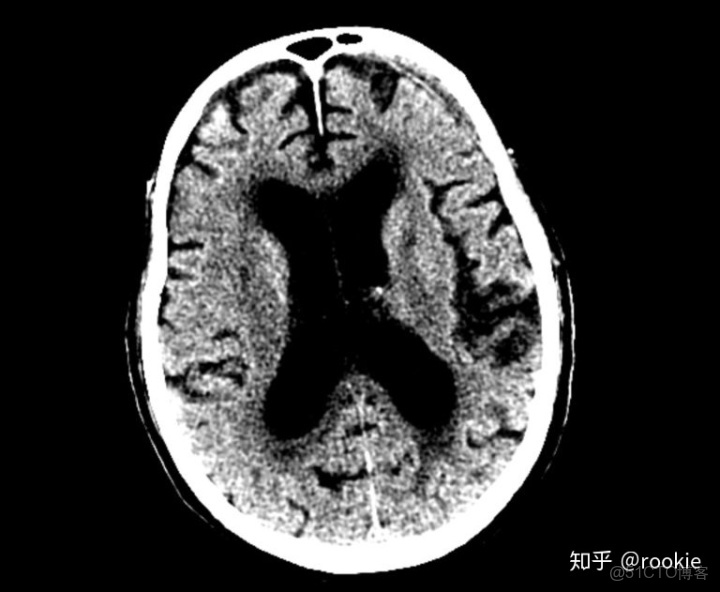

腦窗窗口設置: (W:70,L:30)或(W:70,L:35)優點: 此窗口旨在評估腦實質(通常在非對比掃描中),並且在拾取顱內出血時特別敏感,窗口狹窄且水平接近預期的腦出血密度。

CLAHE算法增強局部對比度的X光圖像增強效果對比_f5_15

腦窗是用來評估腦實質,經常被用來評估顱內出血,在這張圖片上有一個左額葉的慢性硬膜下血腫。